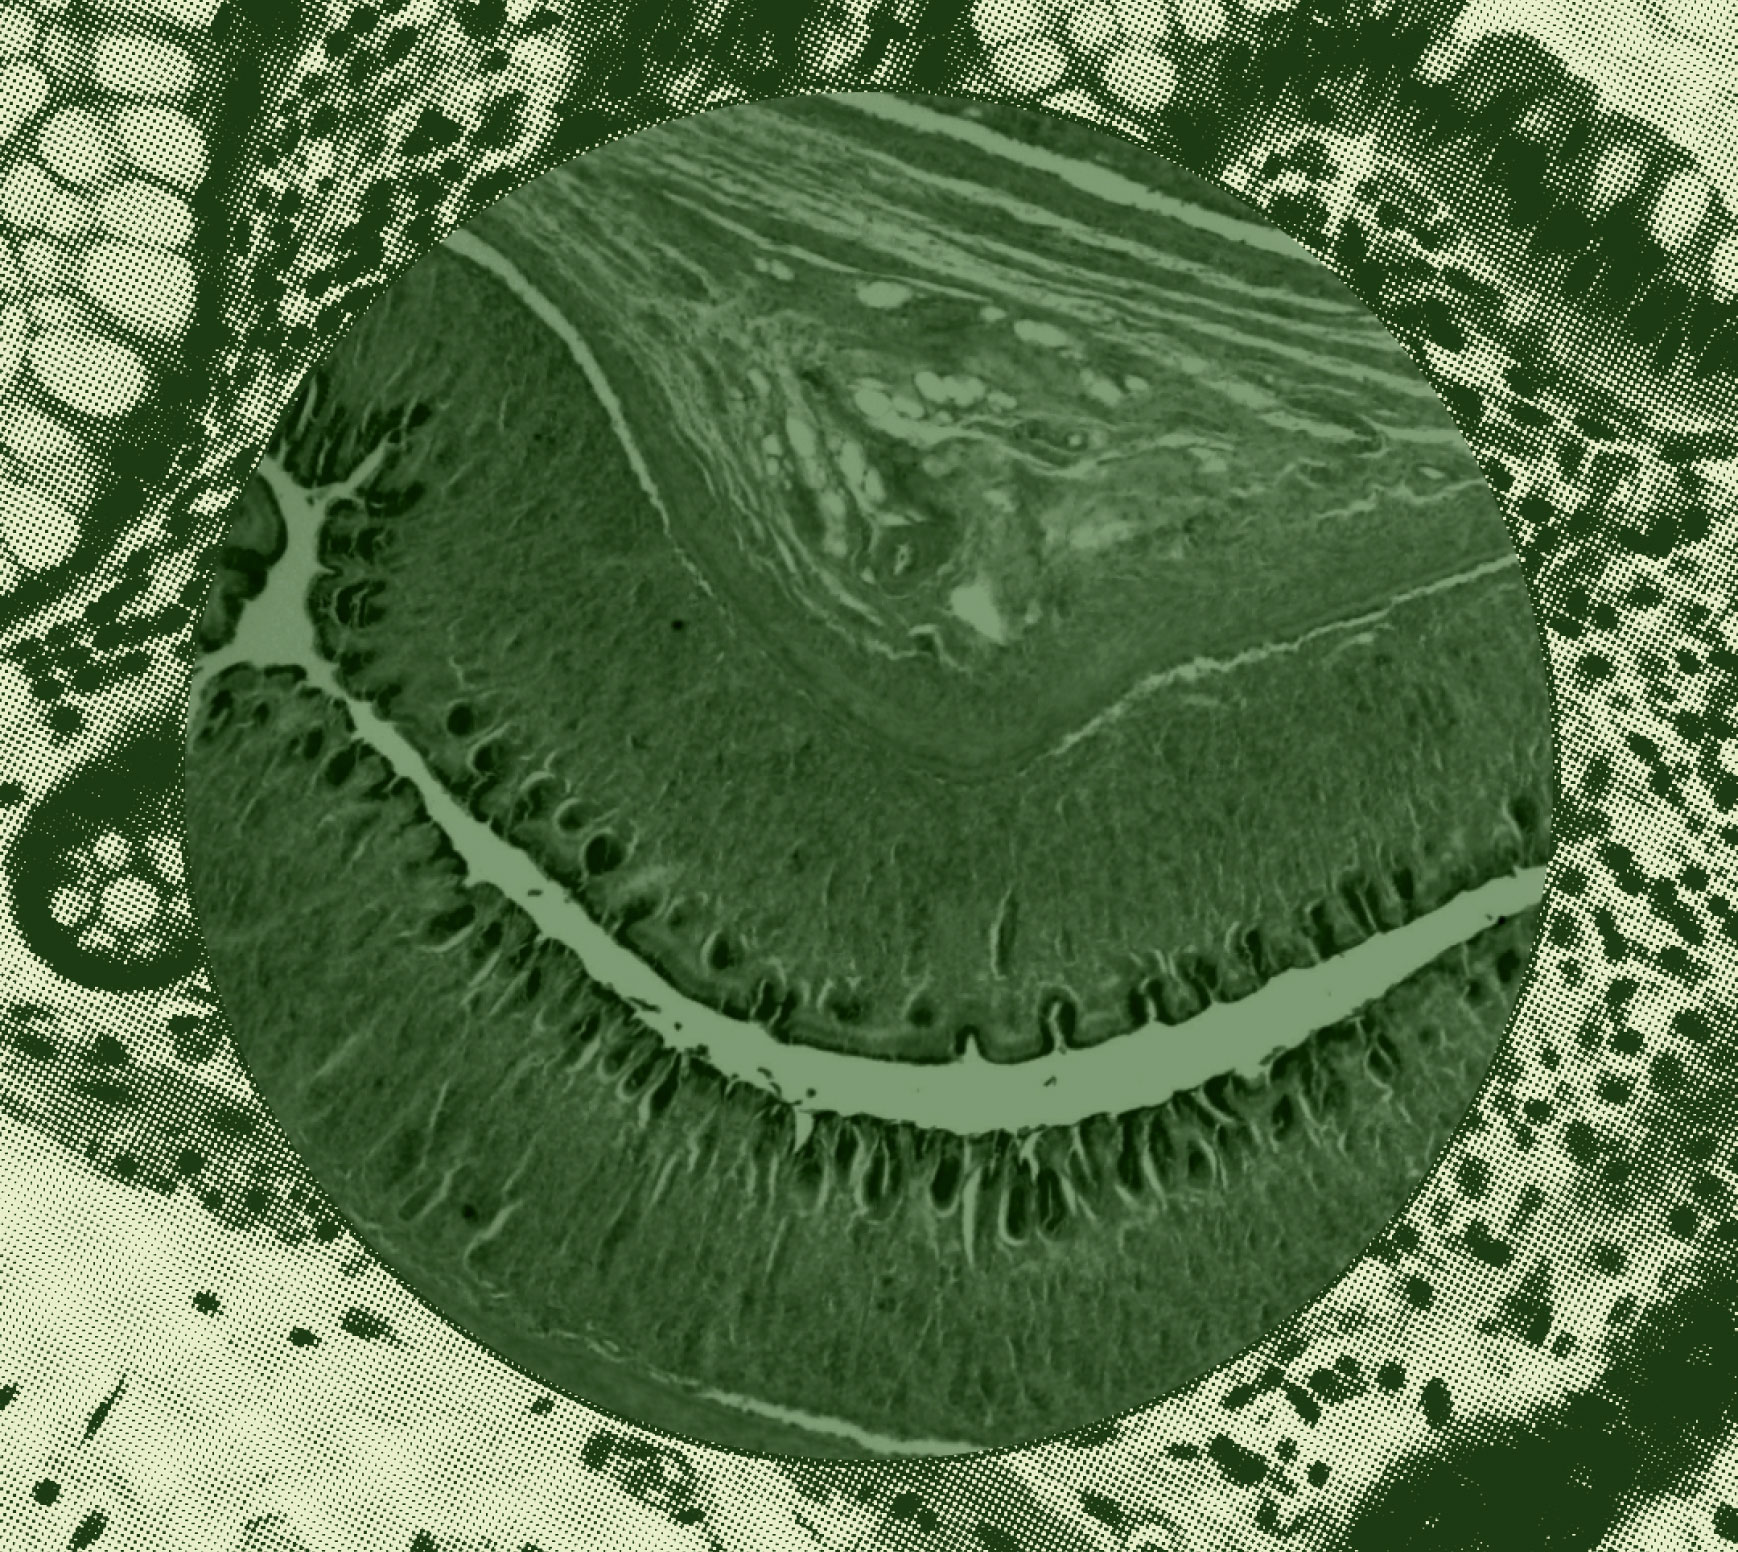

- The mechanical barrier. This consists of a single layer of intestinal epithelial cells, held together by structures called tight junctions. Tight junctions are intercellular connectors that form scaffolding in the gut barrier to reinforce its’ integrity and keep out foreign materials and contaminants. (Fun fact: your resident microbes also support the presence of tight-junctions).

By nature, the gut is permeable, to allow essential inputs to pass through into the body. However, if the gut barrier is damaged or compromised, the permeability of the gut can increase, allowing substances that don’t belong in your body to enter the bloodstream. This is known as intestinal hyperpermeability, leaky gut, or gut barrier dysfunction.

Another key area that researchers are looking at is the role of the gut microbiome in gut barrier function. Homeostasis of the gut barrier depends on the relationship between gut microbiota and the intestinal epithelium. Dysbiosis of the gut microbiota (an imbalance in the composition) could contribute to leaky gut. One way this works: dysbiosis can result in an increased population of pathogenic microbes, which can damage gut epithelial cells.5

Diet is also a major focus when it comes to leaky gut, as dietary components are in frequent contact with the gut barrier, and are likely to play a role in regulating gut microbiota and intestinal permeability. Studies have shown that fats can promote an increase in epithelial permeability. On the other hand, dietary fiber is widely recognized as a protective nutrient for the gut barrier, and also contributes to maintaining a healthy state for gut microbiota. This suggests that Westernized diets, high in fat and lacking fiber, could impair intestinal barrier function.5

The best way to support your gut barrier is to take care of your overall digestive and gastrointestinal health. One simple place to start: probiotics. Certain probiotic strains have demonstrated the ability to influence mucus composition and enhance the gene expressions involved in tight junction signaling.7 Translation: they can promote the integrity and “tightness” of your gut barrier.